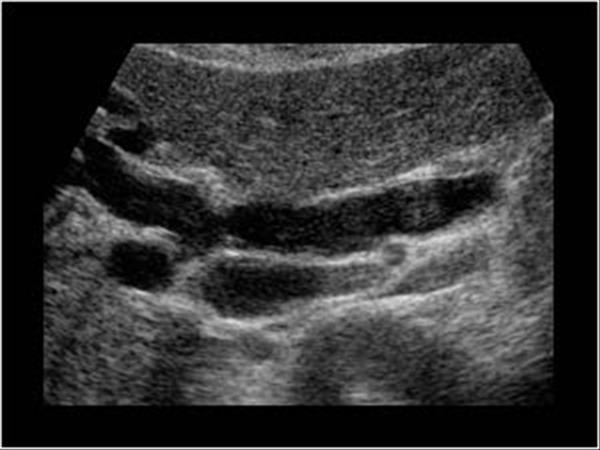

What is Polycystic liver disease?

This is an autosomal dominant genetic disease in which multiple small cysts cover the liver. 60% of patients with polycystic liver disease will have polycystic kidney disease.

What is the sonographic appearance of Polycystic liver disease?

Anechoic

Thin well-defined walls

Posterior

enhancement

Multiple

Varying in small size